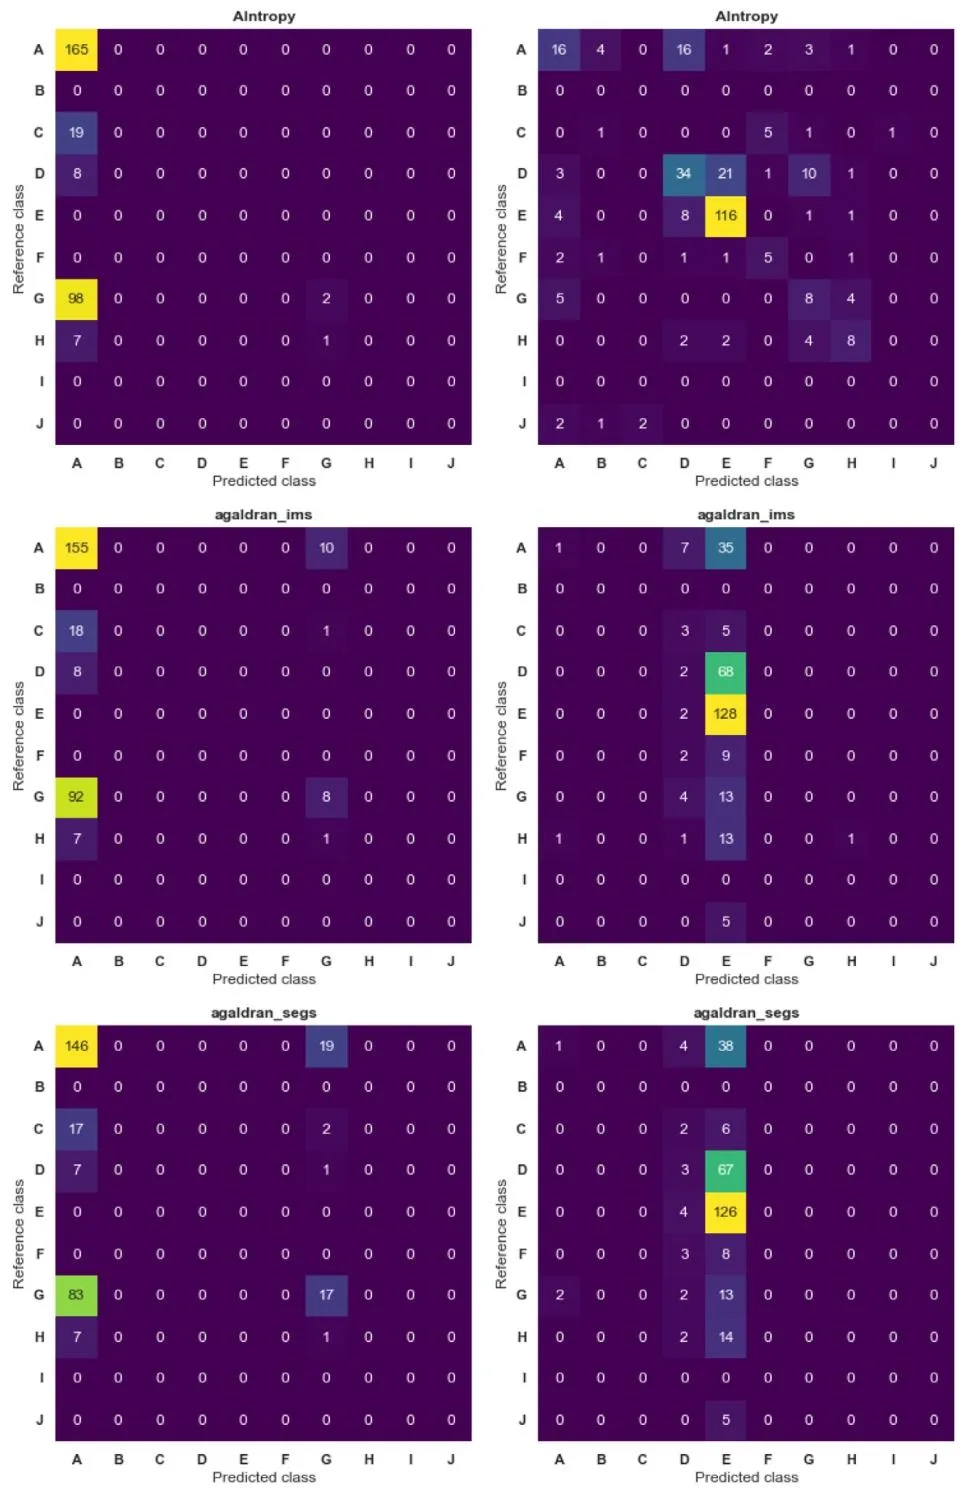

Fig. A.1. Confusion matrices of the results per team (AIntropy, agaldran_ims, and agaldran_segs**) for anterior (left column) and posterior (right column) classification. Rowsrepresent reference classes, while columns represent predicted classes. Values in each cell indicate the count of instances classified accordingly

图 A.1. 各团队(AIntropy、agaldran_ims 和 agaldran_segs)在 Willis 环前部(左列)和后部(右列)分类中的混淆矩阵结果行代表参考类别(真实类别),列代表预测类别。每个单元格中的数值表示被分到相应类别的样本数量